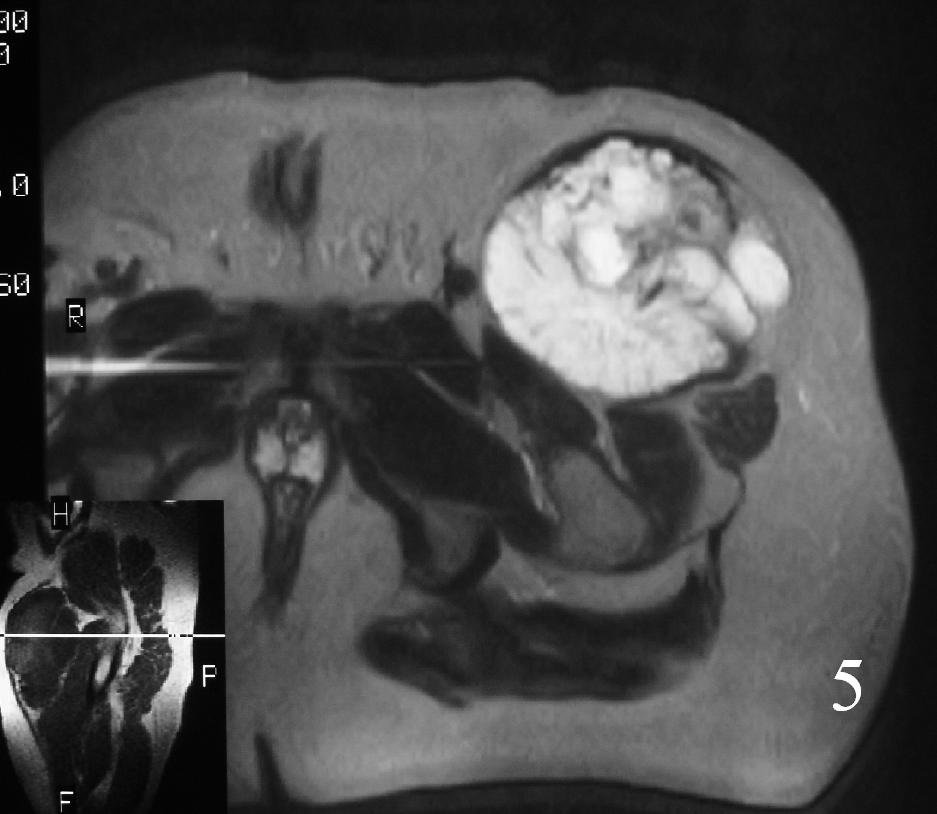

MRI (Fig. 3-7)

Fig. 5

Fig. 3-7 Axial MRI of the lower extremity shows an extraskeletal soft tissue chondrosarcoma in different sequences with and without contrast (Fig. 3, 4, 5). Sagittal MRI (Fig. 6, 7) T1 with-without contrast demonstrates enhancement of the mass